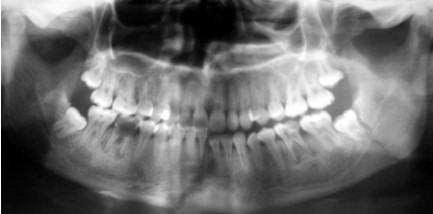

Fig 2: Coronal C.T of displaced angle fracture associated with impacted lower third molar

In this study, 7 cases associated with impacted third molar represented sever displacement of the angle fracture (figure 1, 2) and interfered with achievement of reduction. In four cases, extraction of the impacted lower third molar was done to achieve good reduction at the fracture site. The remaining three cases that were treated without extraction of the lower third molar required more time to obtained good reduction (time range from 30-45 minutes) and exhibited postoperative infection and delayed healing in the fracture site and underwent a second operation for removal of the lower third molar.

In our study, the presence of completely impacted lower third molar provided more risk not only to the fracture but also to degree of the displacement of the fracture site because the tooth occupies more osseous space which could affect the postoperative result. This result agreed with the result of the study that was done by Reitzik et al (22) .